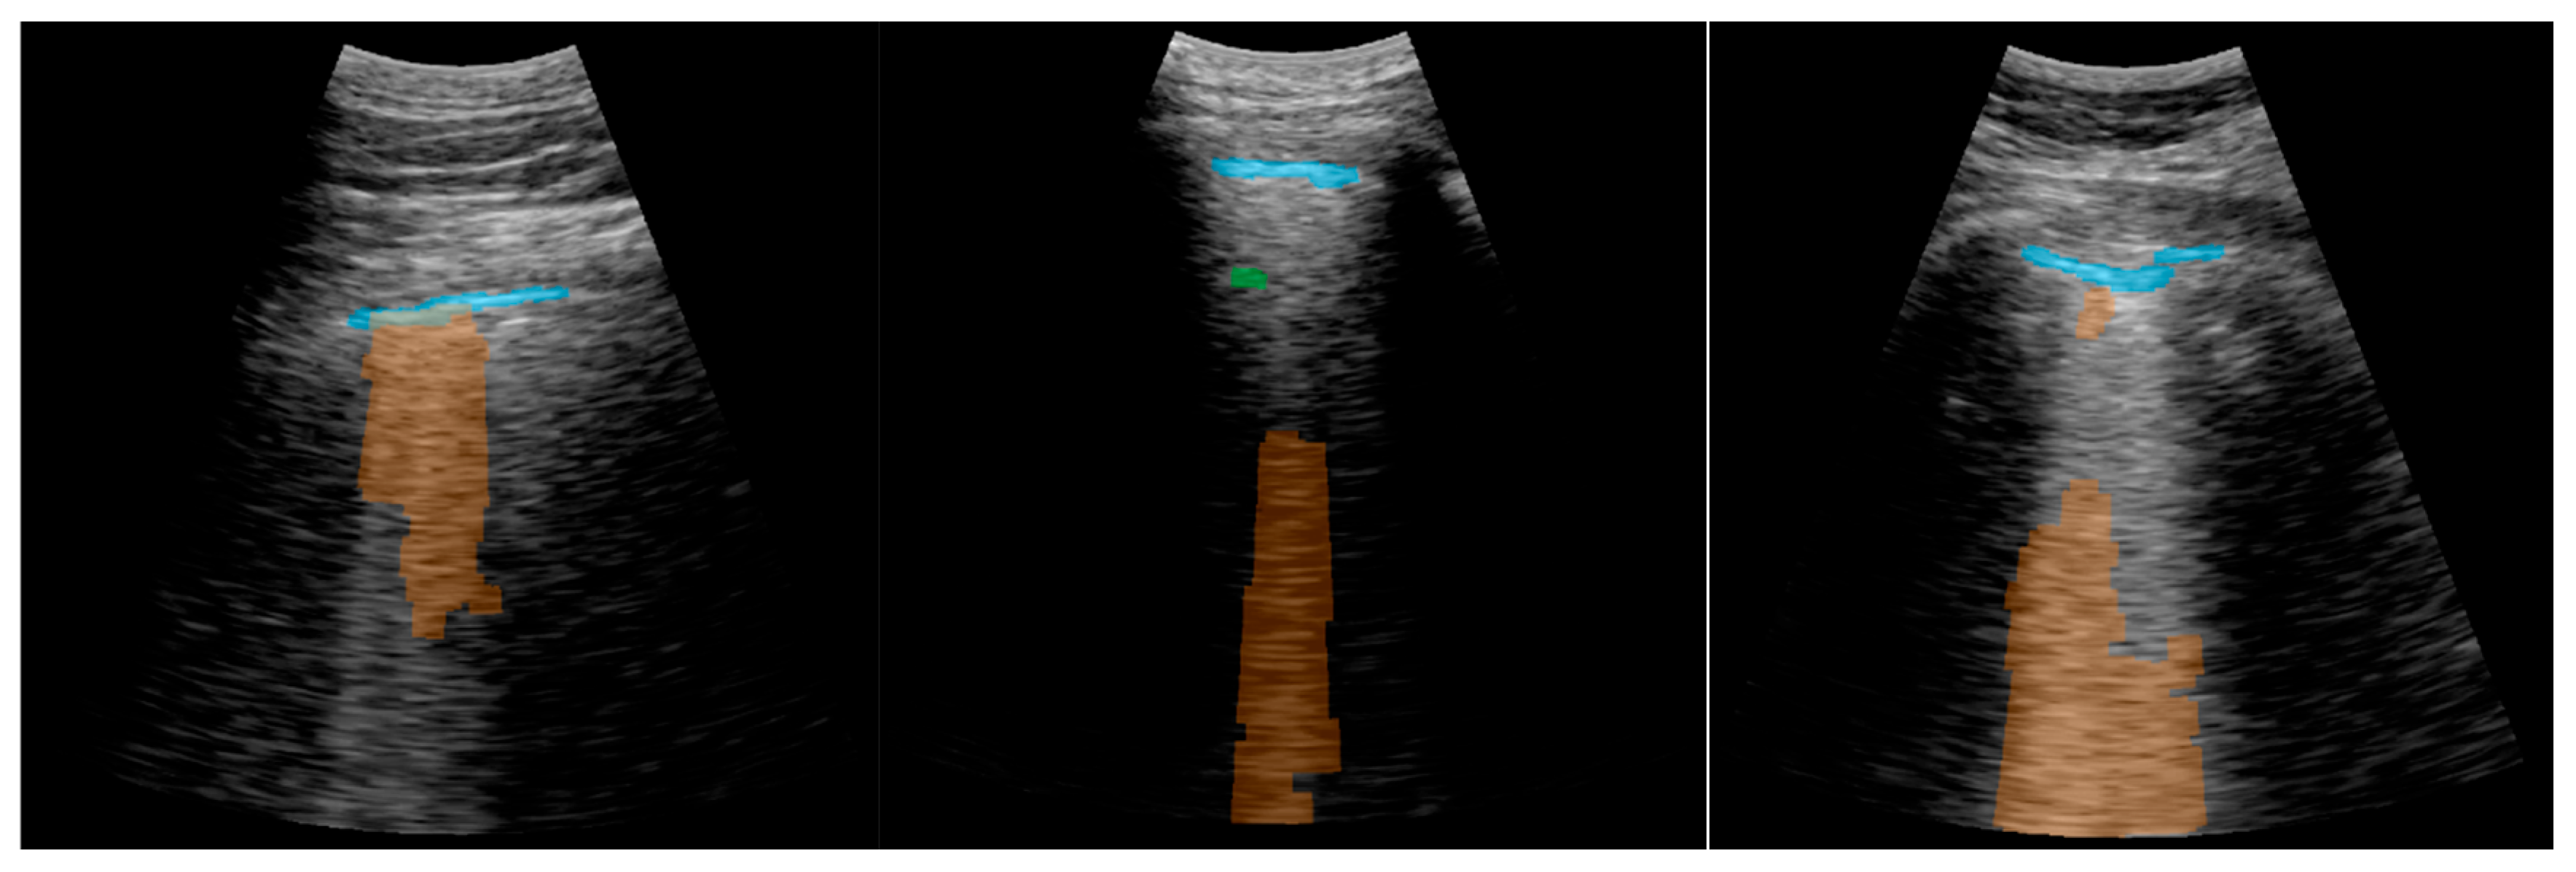

3.2. Real-Time Implementation Results

| Consolidations | B-Lines | A-Lines | Normal Lung | |

|---|---|---|---|---|

| Accuracy (%) | 97.81 | 88.74 | 65.79 | 88.74 |

| False positives (%) | 0.44 | 4.09 | 23.54 | 7.16 |

| False negatives (%) | 1.75 | 7.16 | 10.67 | 4.09 |

| Accuracy (%) | 89.29 | 92.86 | 66.07 | 92.86 |

| False positives (%) | 3.57 | 1.79 | 26.79 | 5.36 |

| False negatives (%) | 7.14 | 5.36 | 7.14 | 1.79 |